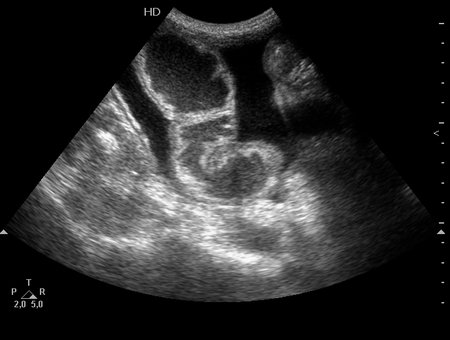

Кишечная непроходимость, асцит. Ileus, ascitis.

Женщина, боли в животе. Оперирована ранее по поводу опухоли толстой кишки.